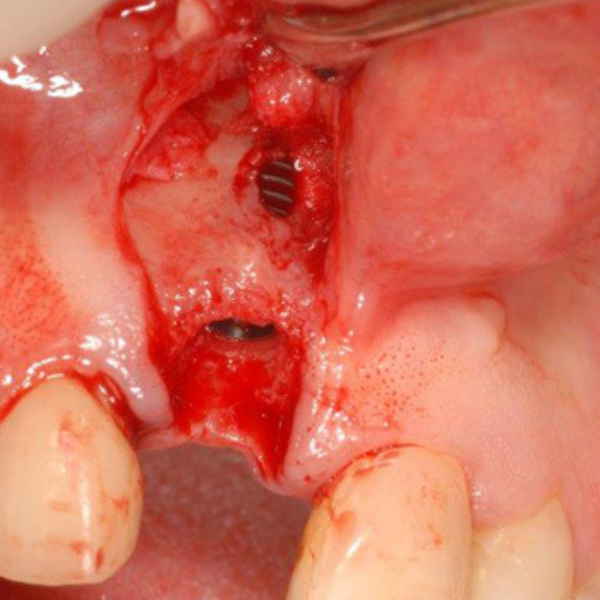

Resorbable Suture Tenting

Pain from a mobile upper right central incisor that had received trauma approximately ten years prior to presentation.